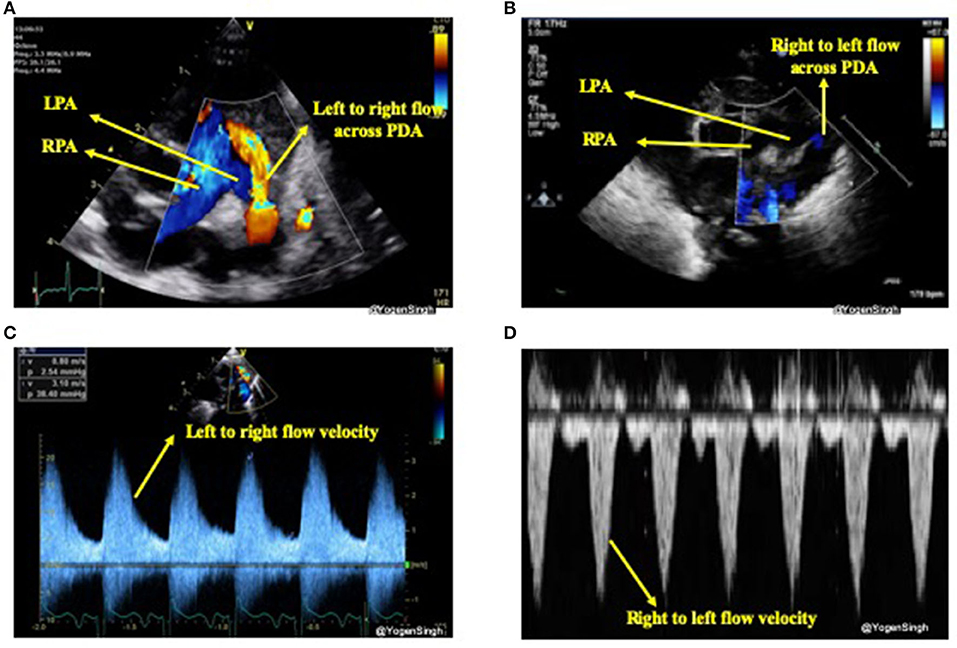

The direction of the ductal shunt depends upon the relationship between the pulmonary and systemic pressures. It is assessed using color Doppler and direction of blood flow across ductus arteriosus is normally left to right, from the aorta (high systemic pressure) to the pulmonary artery (low pulmonary pressure) but it can be right to left or bi-directional when there is high pulmonary vascular resistance or when there is anatomical cause (due to certain CHDs). With conventional setting left to right shunt is seen as red jet while right to left shunt is seen as blue (21). A right-to-left shunt across the PDA is more difficult to see because color Doppler will show it as a blue jet, blood going toward aorta from pulmonary end, similar to branch pulmonary arteries. Color compare or simultaneous mode can be very helpful in such situation. Bi-directional flow is often seen during transitional circulation or when the pulmonary artery pressures are equal to systemic pressures (21). Shunt direction can also be assessed using pulse or continuous wave Doppler where left to right shunt is seen above the baseline (blood coming toward the probe) while right to left shunt is seen below the baseline (blood going away from the probe) (15, 21) (Figure 4).

Figure 4. Assessment of PDA shunt direction on color flow and with Doppler application. (A) Left to right shunt seen as red (blood coming toward probe) while blood in branch pulmonary arteries seen as blue (blood going away from probe); (B) showing right to left shunt seen as blue color—similar to branch pulmonary arteries in a view “three legged trouser;” (C) Doppler assessment showing left to right shunt (above the baseline as blood coming toward the probe); and (D) Doppler assessment showing right to left shunt (below the baseline as blood going away from the probe). LPA, left pulmonary artery; RPA, right pulmonary artery; PDA, patent ductus arteriosus.